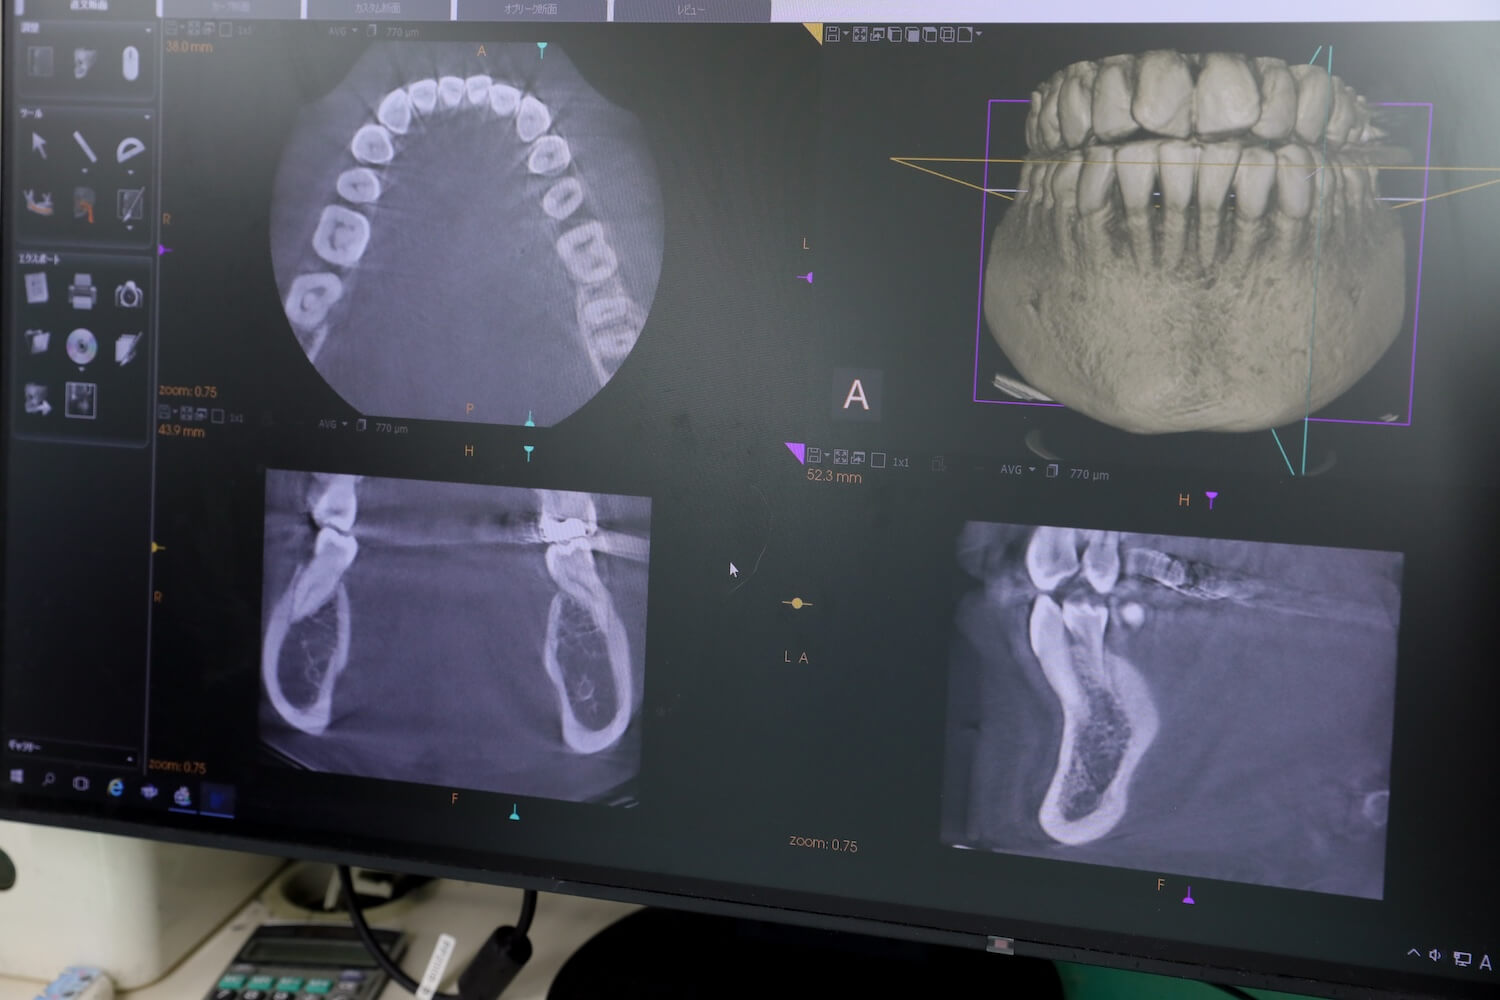

大半の症例は当院で対応可能です。ただし、CTによる精密検査の結果、深く埋没し過ぎていたり、神経に近接し過ぎていたりしてリスクが高いものは、入院や全身麻酔を行える病院をご紹介します。